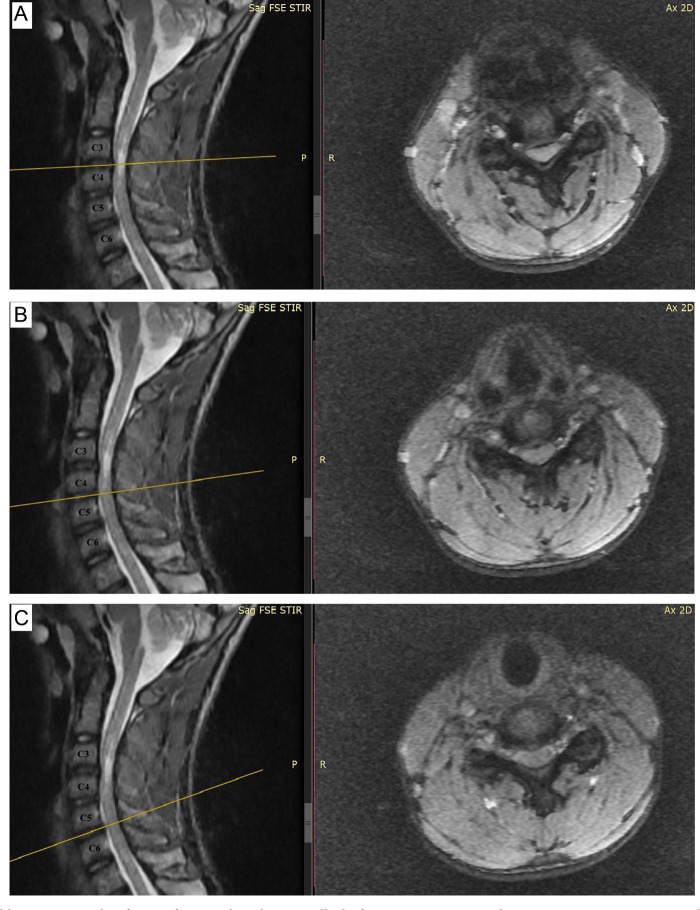

脊髓型颈椎病是一种很少报道的儿童运动或神经肌肉疾病患者。我们在此报告一例罕见的脊髓型颈椎病,患者为一名14岁的健康男孩,他之前是一名接受颈椎椎板成形术的患者,这是由于颈椎管狭窄导致的多节段椎间盘突出。患者提出了痉挛和共济失调的步态与以前的诊断挑战的诊所。磁共振成像显示颈椎退行性改变主要表现在C3-C4和C4-C5水平,t2加权图像上伴有椎管狭窄和中央高信号索异常。采用C3-C4开门椎板成形术。手术后神经症状和体征显著改善。随后,颈椎计算机断层扫描和磁共振成像显示,在5年的随访中,颈椎脊髓得到了良好的减压,活动范围得以保留。我们的结论是,尽管这种情况非常罕见,但在诊断青少年患者步态和平衡障碍时应考虑颈椎病。

Cervical myelopathy is a condition that is rarely reported in pediatric patients who have movement or neuromuscular disorders. We, herein, present a rare case of cervical myelopathy observed in a 14-year-old patient, who was previously a healthy boy treated with cervical laminoplasty, which was caused by cervical spinal canal stenosis based on multiple level disc herniation. The patient presented to the clinic with spastic and ataxic gait with previous diagnostic challenges. Magnetic resonance imaging showed cervical degenerative changes mainly marked at the C3-C4 and C4-C5 levels, along with canal narrowing and a central high signal cord abnormality on T2-weighted images. A C3-C4 open-door laminoplasty surgery technique was performed. The neurological symptoms and signs improved dramatically following surgery. Subsequently, cervical computed tomography and magnetic resonance imaging showed good decompression of the cervical spinal cord during the 5 years of follow-up with the preservation of the range of movement. We concluded that though it is pretty rare, cervical myelopathy should be considered in diagnosing adolescent patients with gait and balance disorders.